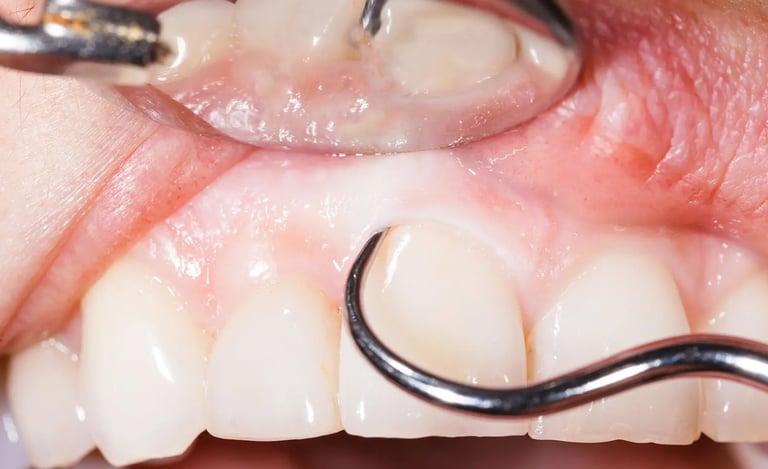

Deep Cleaning, also called Scaling and Root Planing (SRP), is a non-surgical treatment for gum disease. During this procedure, the hygienist cleans deep under the gums and smooths the roots of your teeth. This reduces inflammation, stops infection from getting worse, and helps gums heal and reattach to the teeth.

Deep cleaning, also known as scaling and root planing, is used to treat gum disease by removing plaque and bacteria from below the gum line and smoothing the tooth roots to help gums heal properly. Depending on the severity of the condition, the treatment may be completed in sections (such as half-mouth or quadrant visits) to ensure comfort and thorough care. After deep cleaning, ongoing periodontal maintenance visits every 3–4 months are essential to keep gum disease under control, as regular cleanings are not sufficient once periodontal issues are present.